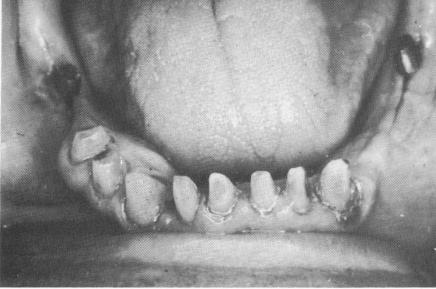

This patient's teeth were unattractive and in poor condition (Fig. 11-50). His remaining mandibular teeth were prepared for full crown restorations. After the castings were fitted over the abutment teeth and all occlusal adjustments made, local anesthesia was given, one side at a time. The first blade was inserted in the right mandibular molar area (Fig. 11-51) and the second in the left (Fig. 11-52). The sites were then sutured closed (Fig. 11-53), and a prefabricated temporary splint lined with a soft tissue conditioner was placed over the abutment teeth and implant posts (Fig. 11-54).

Fig. 11-53. The site sutured closed.